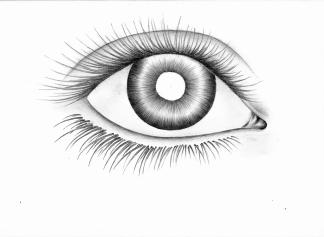

EPITHESE ORBITAIRE

Une épithèse orbitaire est une prothèse utilisée pour remplacer l'œil ou pour reconstruire la zone de l'orbite après une perte d'œil ou des dommages importants à la région orbitale (la cavité dans laquelle l'œil se trouve).